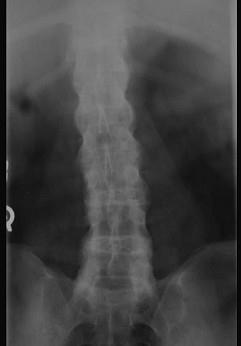

问题 男,21岁,下腰不适,晨起加重半年余,X线检查如图,请选出最可能的诊断 ( )

选项 A、化脓性脊柱炎 B、阻滞椎 C、脊椎退行性变 D、强直性脊柱炎 E、类风湿关节炎

答案 D